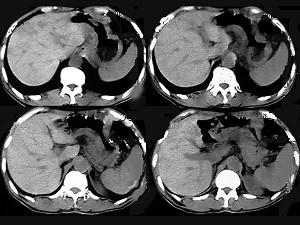

问题 患者50岁,男性,中上腹饱胀、疼痛半年,消瘦,CT扫描如图,应诊断为()

选项 A.淋巴瘤 B.胃腺瘤 C.胃癌 D.胃窦溃疡梗阻 E.胃平滑肌瘤

答案 C